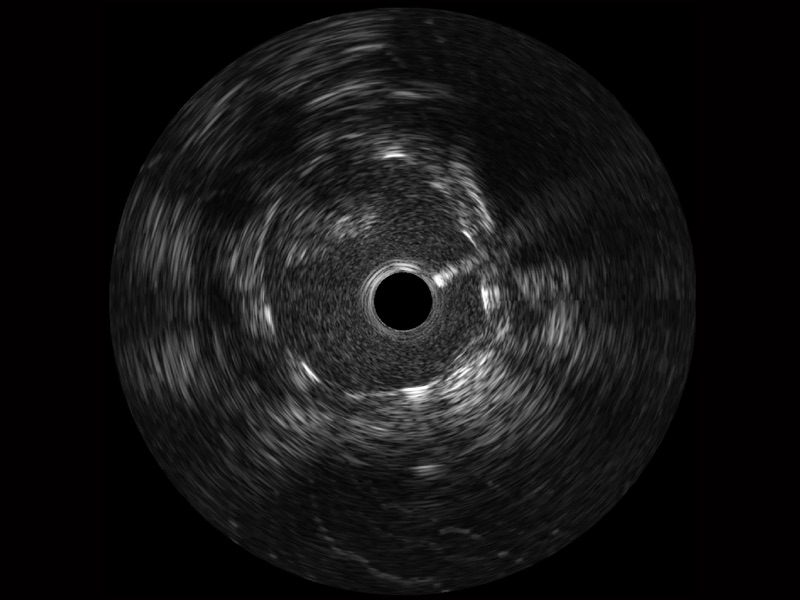

球速体育入口宽频IVUS图像

传统IVUS图像

对比传统IVUS导管成像,球速体育入口宽频IVUS图像的近场支架梁显影更细腻,远场中膜外血管仍清晰可辨,兼顾远中近,兼顾分辨力与穿透深度